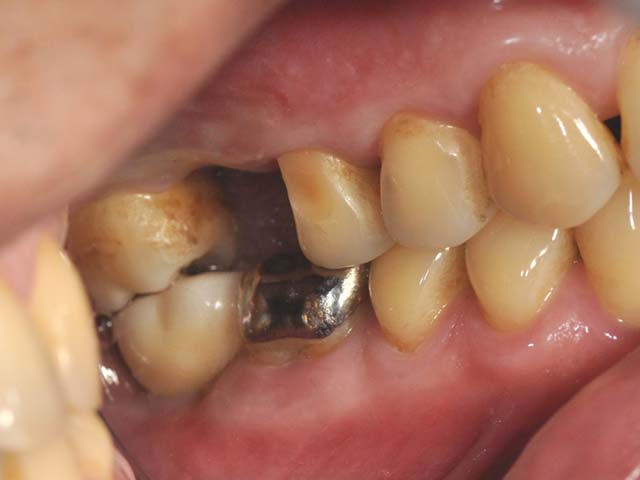

鼻竇增高術(垂直)+植牙 首頁 案例分享 人工植牙 鼻竇增高術(垂直)+植牙 鼻竇增高術(垂直)+植牙 術前評估 PRF(使用法國離心機,萃取出有益於傷口癒合的血小板,並加以濃縮) 鼻竇增高術 從植牙傷口置入萃取的PRF,將鼻竇往上抬升,再植入骨粉,以利植牙。 電腦斷層—術前,術中,假牙完成